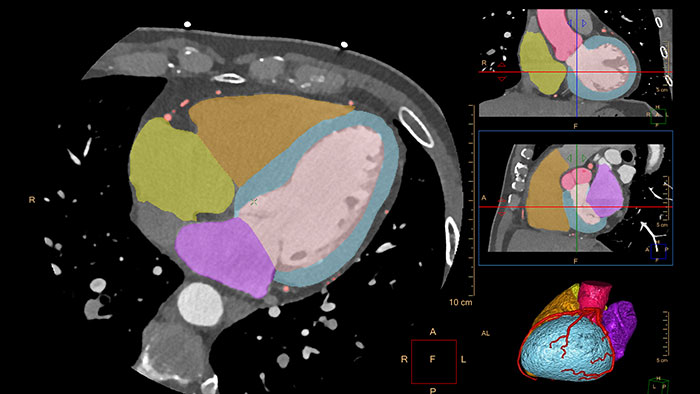

CT cardiac analysis

This application is based on an automatic 3D model-based whole-heart segmentation and zero-click coronary artery segmentation. This enables automatic extraction and visualization of the entire coronary tree.

Provides visual and quantitative assessment of segmented, low-attenuation defect areas within the myocardium from a single, gated cardiac CTA scan (retrospectively-gated spiral or Step and Shoot Cardiac). The CT Myocardial Defect Assessment application is based on the robust, automatic, model-based, whole-heart segmentation from the CT Comprehensive Cardiac Analysis (CCA) application.

- color maps shown in short-axis views - segmentation maps shown on short-axis and polar plots, displayed along with long-axis reference images - volumetric visualization of coronary arteries along with segmentation maps displayed as an overlay on top of a 3D myocardial surface.